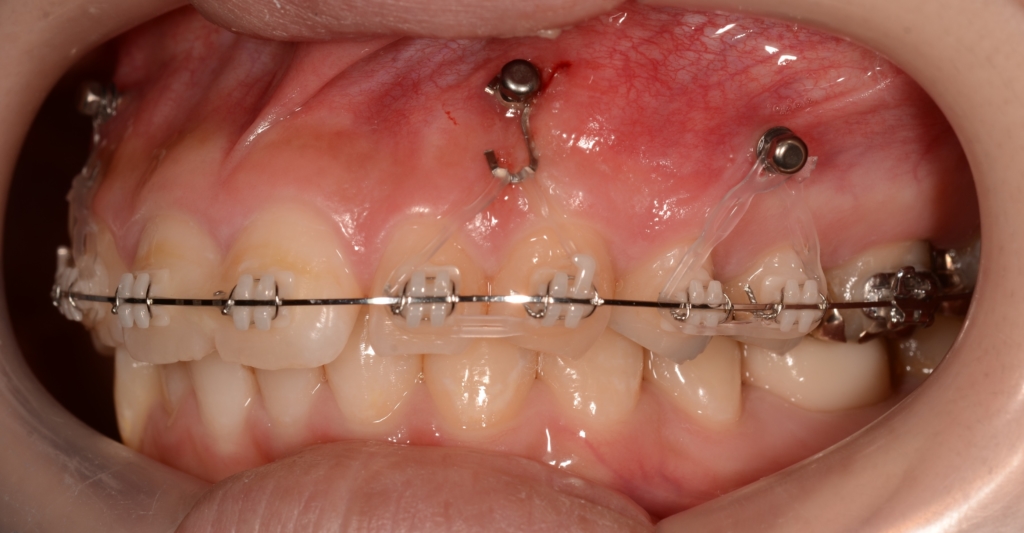

ステップが進み歯列が揃ったところで、ガミースマイル改善のために、上顎にアンカースクリューを植立することにしました。

部位は、上顎の口蓋の真ん中、臼歯部(左右側とも)と前歯部の頬側、になります。

アンカースクリューを用いて矯正力を加えることで、上顎歯列全体を圧下させて、ガミースマイルの改善を図ります。

順調に矯正治療は進み、ガミースマイルはほぼ改善されました。

治療に伴う歯肉の変化をお見せしましょう。

上段が圧下治療開始時点、下段が圧下治療終了後 になります。

アンカースクリューは動きませんから、上記の写真を見れば、圧下治療に伴い前歯が周りの歯肉ごと押し込まれて歯肉の見え方が狭くなったことが一目瞭然で分かると思います。